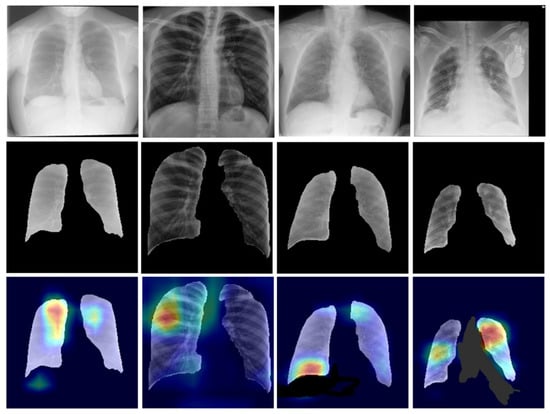

3.2.3. Heatmap Visualization: An Explainable AI Model